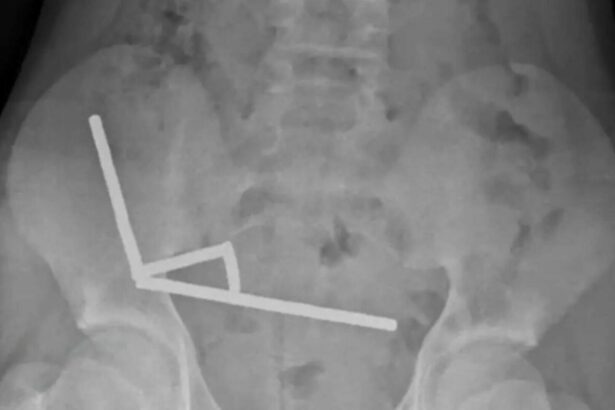

Băiat de 13 ani, operat după ce a înghițit magneți